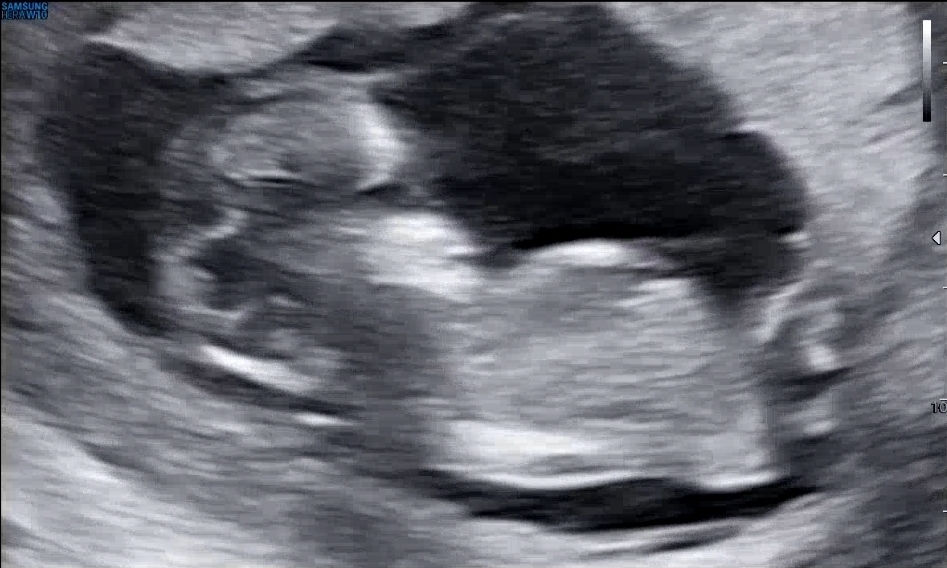

13주2일 각도법 봐주세요!

13주2일 입니당! 각도법 한번만 봐주시면 감사하겠습니당 ☺️